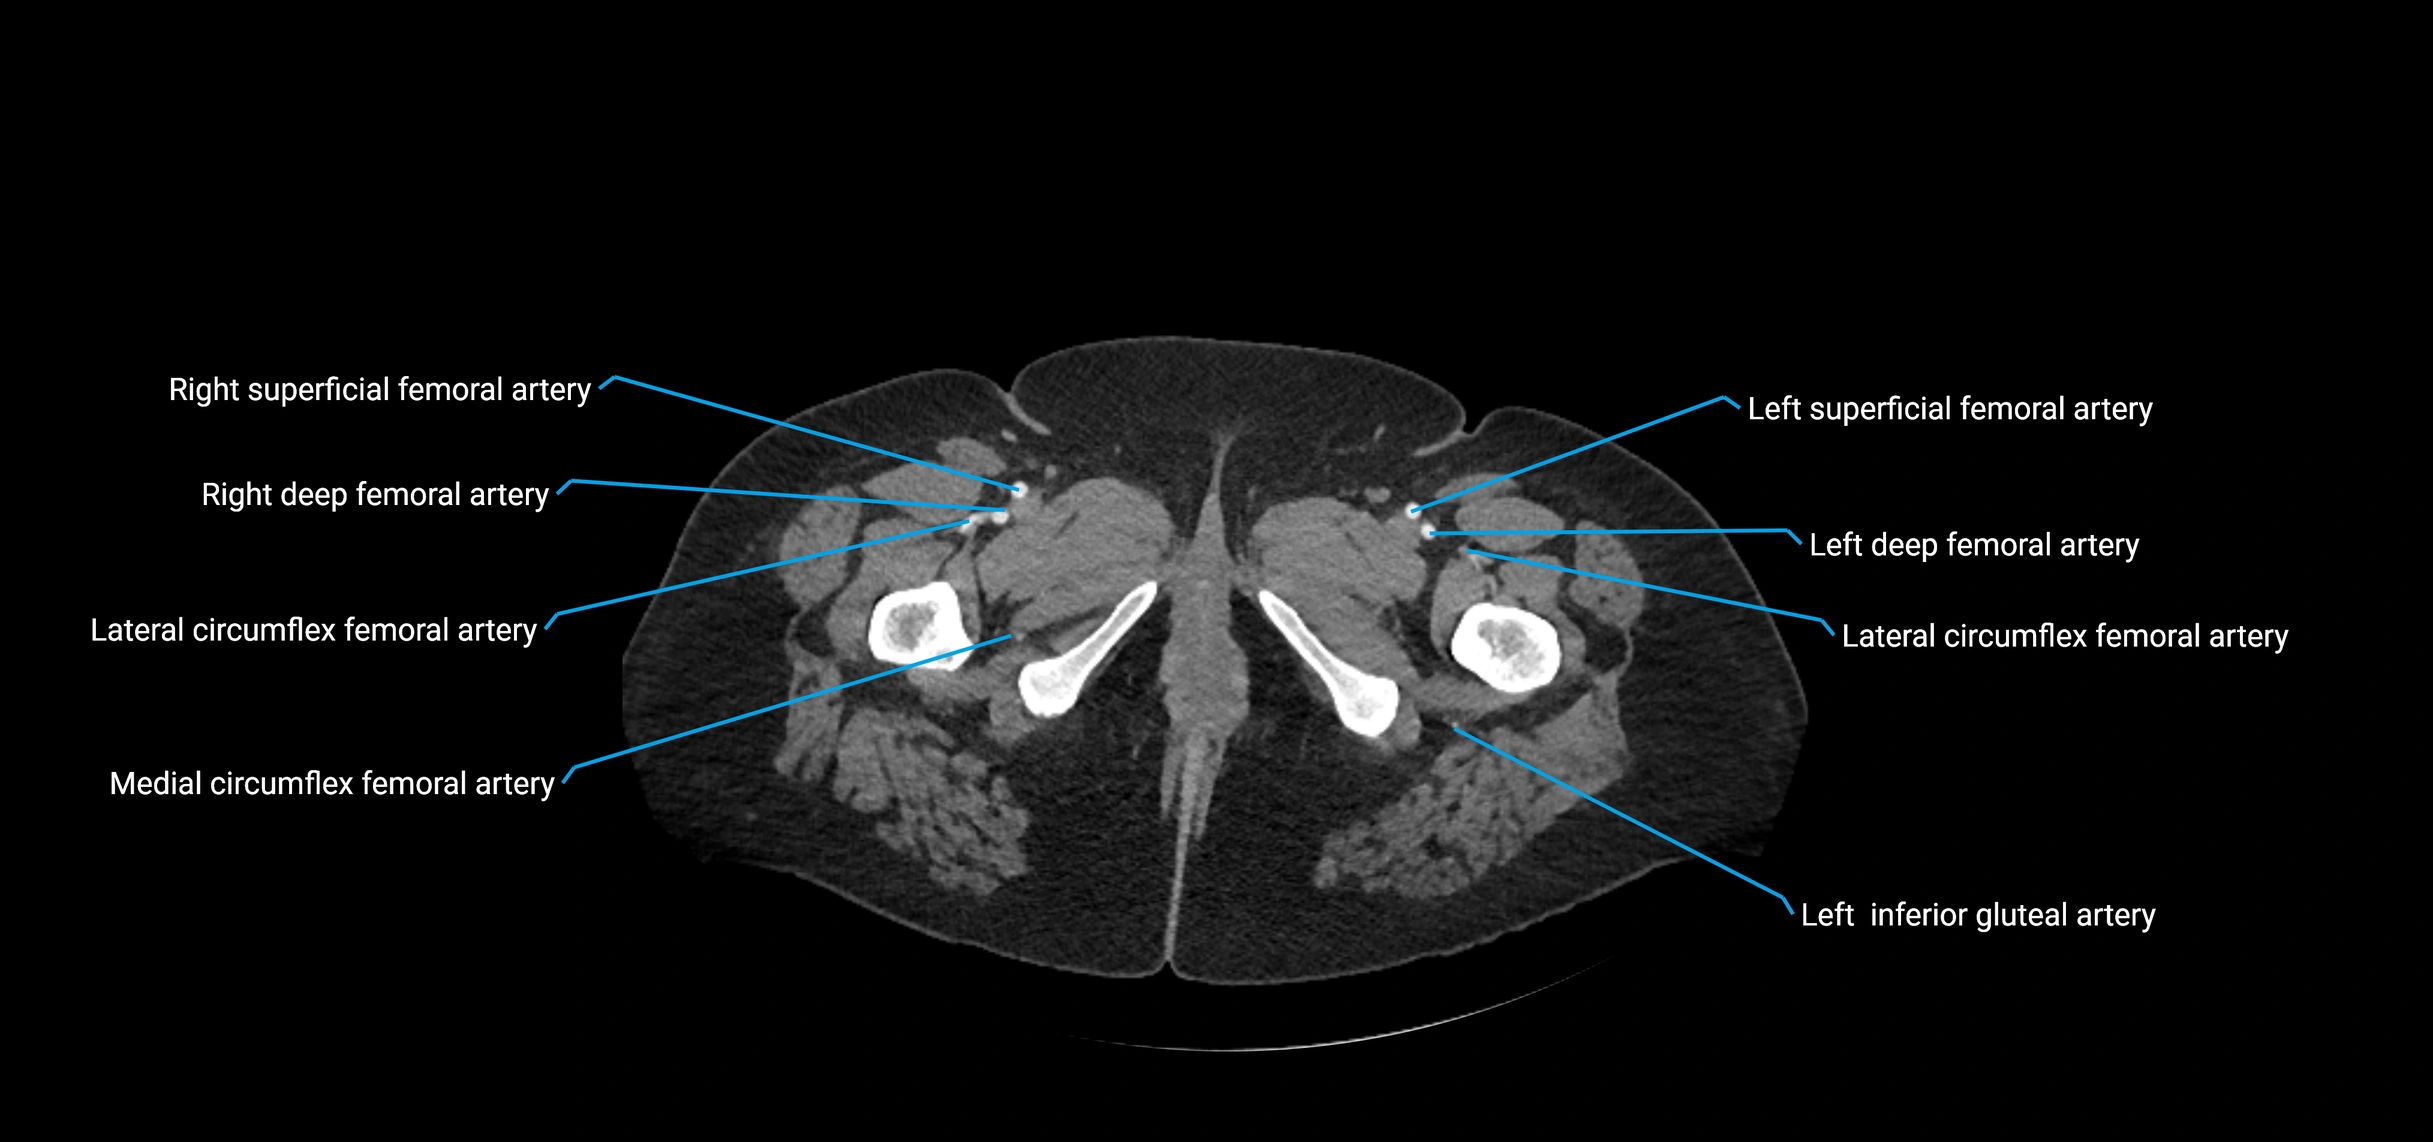

CT images

image